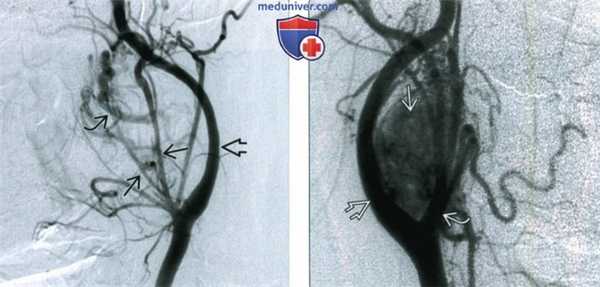

Ангиография выявляет гиперваскуляризацию опухоли. Для уменьшения интраоперационной кровопотери проводится предварительная эмболизация микрочастицами.

5. Ангиография:

• На ангиограммах в раннюю артериальную фазу - расщепление внутренней и наружной сонных артерий

• Длительное, интенсивное накопление контраста опухолью

• Феномен «ранней венозной фазы» из-за наличия артериовенозного сброса

• Чаще всего питается из восходящей глоточной артерии

(Слева) Ангиография общей сонной артерии, боковая проекция. В артериальную фазу визуализируются крупные питающие сосуды. Также имеется артериовенозный сброс, который приводит к раннему появлению на изображении одной из увеличенных вен. Внутренняя сонная артерия смещена кзади.

(Справа) Ангиография общей сонной артерии, боковая проекция, поздняя артериальная фаза. Между наружной и внутренней сонными артериями определяется каротидная параганглиома.